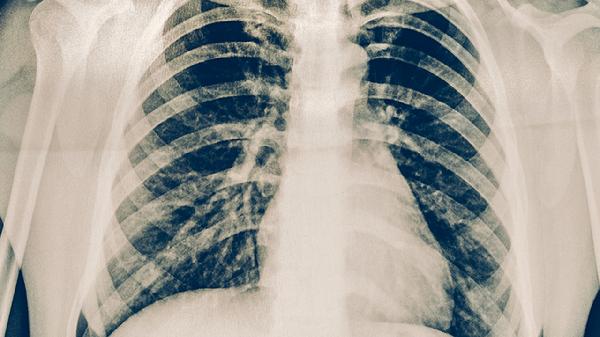

肺结核的治疗强调早期、联合、适量、规律和全程用药,具体采用口服、注射还是二者联用,必须由专科医生根据痰菌检查、药敏试验结果和影像学变化综合决定。患者切勿自行选择或更改治疗方案,应严格遵从医嘱,完成全程治疗,同时注意加强营养、保证休息、做好隔离,定期复查肝肾功能等指标,以最大程度确保疗效并减少并发症。